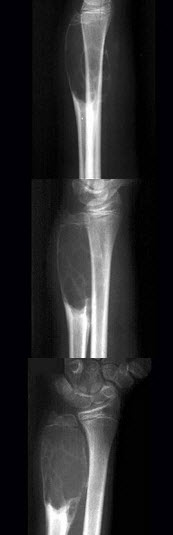

17、单项选择题

男,17岁,来右前臂疼痛,肿胀近2年,2周前疼痛加剧,查体右前臂压痛明显,皮肤稍显红肿,结合图像,最可能诊断是()

A.骨囊肿

B.骨巨细胞瘤

C.动脉瘤样骨囊肿

D.软骨瘤

E.骨血管球瘤